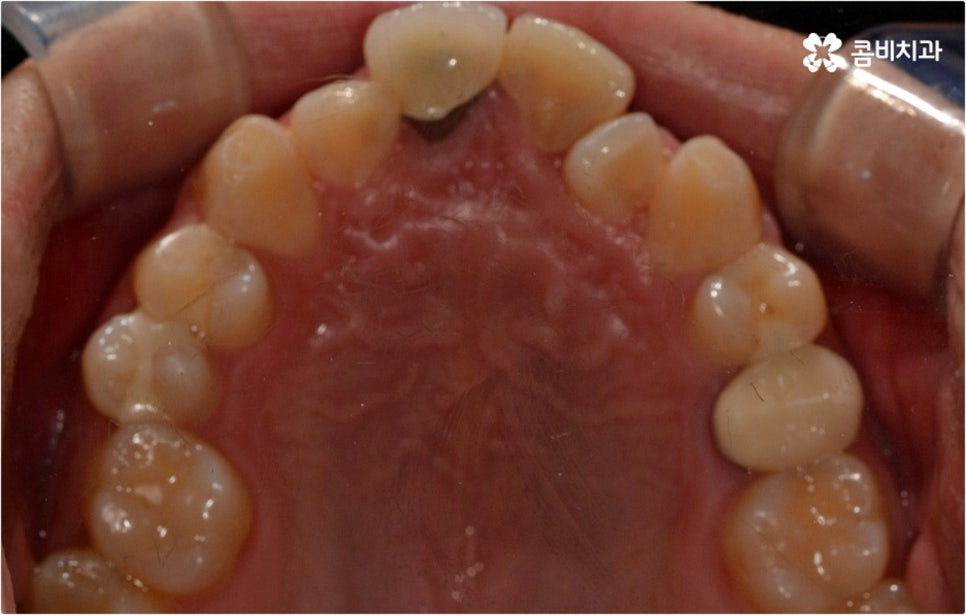

덧니의 원인에는 여러 가지가 있을 수 있으나 보통 혼합치열기, 즉 유치가 영구치로 교체되면서 둘이 공존하는 시기인 6~13세 사이에 교체가 원활하게 이루어지지 않는 것 (유치가 너무 빨리 빠져 충분한 공간 유지가 되지 않거나 너무 늦게까지 빠지지 않아 영구치와 겹쳐 나게 됨), 선천적으로 치아가 나올 공간이 부족하거나 영구치가 너무 크게 자라는 것 등을 원인으로 발생하는 경우가 많아 초등학교 고학년에서 중학교 저학년까지의 시기를 덧니교정 치료를 위한 정밀 검진의 골든 타임으로 여기고 있습니다.

덧니교정 시 환자분들의 상황에 따라 치아 이동에 필요한 공간이 부족하지 않다면 비발치 교정이 가능한데요, 이런 경우 치아 사이를 살짝 갈아서 여유 공간을 만드는 치간 삭제 방법, 마지막 어금니를 후방으로 이동시키는 방법, 그리고 악궁 확장 장치를 사용해 치아 사이를 벌려주는 방법 등 다양한 방법으로 공간을 만들어 치열을 가지런하게 바로잡아 줄 수 있습니다. 이때 환자분들의 구강 상태, 즉 악궁 크기 대비 치아의 크기, 치아가 겹친 정도, 덧니의 위치와 개수 등을 자세하게 검진한 다음 치아가 이동할 충분한 공간이 확보되지 않는다면 발치 교정을 하게 될 거예요.